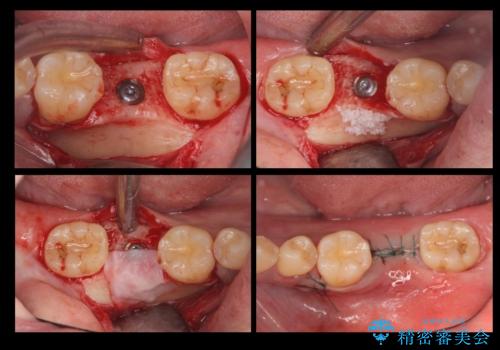

- 下の前歯が1本生まれつき少なかったため、インプラント治療を行いました。

インプラントの前に矯正治療を行い、入れる隙間を確保しました。

ブリッジにすることも可能でしたが、両側の歯が天然歯であること、また、事前に矯正で噛み合わせを整え、幅も確保していたこと、CTにより骨の厚みがある程度あったことを踏まえ、インプラントも可能であるとお話しし、選んでいただきました。

唇側の骨増成もしっかり行い、前歯部インプラントによくある、歯茎が下がって見えることもない、審美的なインプラント補綴ができました。